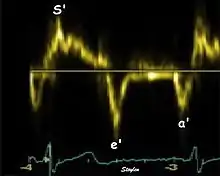

Systolic function

Peak systolic annular velocity (S') of the left ventricle is as close to a contractility measure as you can get by imaging[4] (bearing in mind that any imaging method only measures the result of fibre shortening, without measuring myocyte tension). S' has become a reliable measure of global function[5][6][7][8] It shares the advantage of annular displacement, that it is reduced also in hypertrophic hearts with small ventricles and normal ejection fraction (HFNEF), which is often seen in Hypertensive heart disease, Hypertrophic cardiomyopathy and Aortic stenosis.[9]

Diastolic function

As the ventricle relaxes, the annulus moves towards the base of the heart, signifying the volume expansion of the ventricle. The peak mitral annular velocity during early filling, e' is a measure of left ventricular diastolic function, and has been shown to be relatively independent of left ventricular filling pressure.[12][13][14][15] If there is impaired relaxation (Diastolic dysfunction), the e' velocity decreases. After the early relaxation, the ventricular myocardium is passive, the late velocity peak a' is a function of atrial contraction. The ratio between e' and a' is also a measure of diastolic function, in addition to the absolute values.

During the two filling phases, there is early (E) and late (A) blood flow from the atrium to the ventricle, corresponding to the annular velocity phases. The flow, is driven by the pressure difference between atrium and ventricle, this pressure difference is both a function of the pressure drop during early relaxation and the initial atrial pressure. In light diastolic dysfunction, the peak early mitral flow velocity E is reduced in proportion to the e', but if relaxation is so reduced that it causes increase in atrial pressure, E will increase again, while e', being less load dependent, remains low. Thus, the ratio E/e' is related to the atrial pressure, and can show increased filling pressure,[16][17][18] although with several reservations.[19][20] In the right ventricle this is not an important principle, as the right atrial pressure is the same as central venous pressure which can easily be assessed from venous congestion.[21][22]